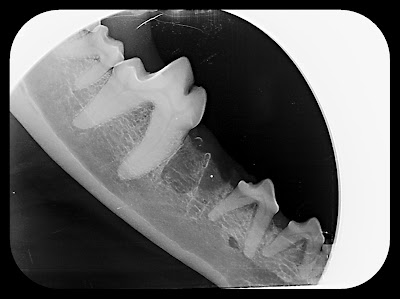

The x-rays only took a few minutes and Dr. Peak called us in to take a look, it turned out that Monty had a resorptive lesion and the one I noticed wasn't as bad as the tooth on the other side that also had the same thing going on. We had no choice but to have both teeth extracted.

Dr. Peak said that the only way to catch a resorptive lesion early is to take an x-ray so there was no way we could have known or prevented it from happening. He estimated that it started about 6 months ago and was probably causing him some discomfort. As you can see in the x-ray the right and left side premolars are being absorbed by the body.

Above is a picture of Monty's premolar. This is the one that looks fine on this side but according to the x-ray this one is worse than the one with the visible problem.